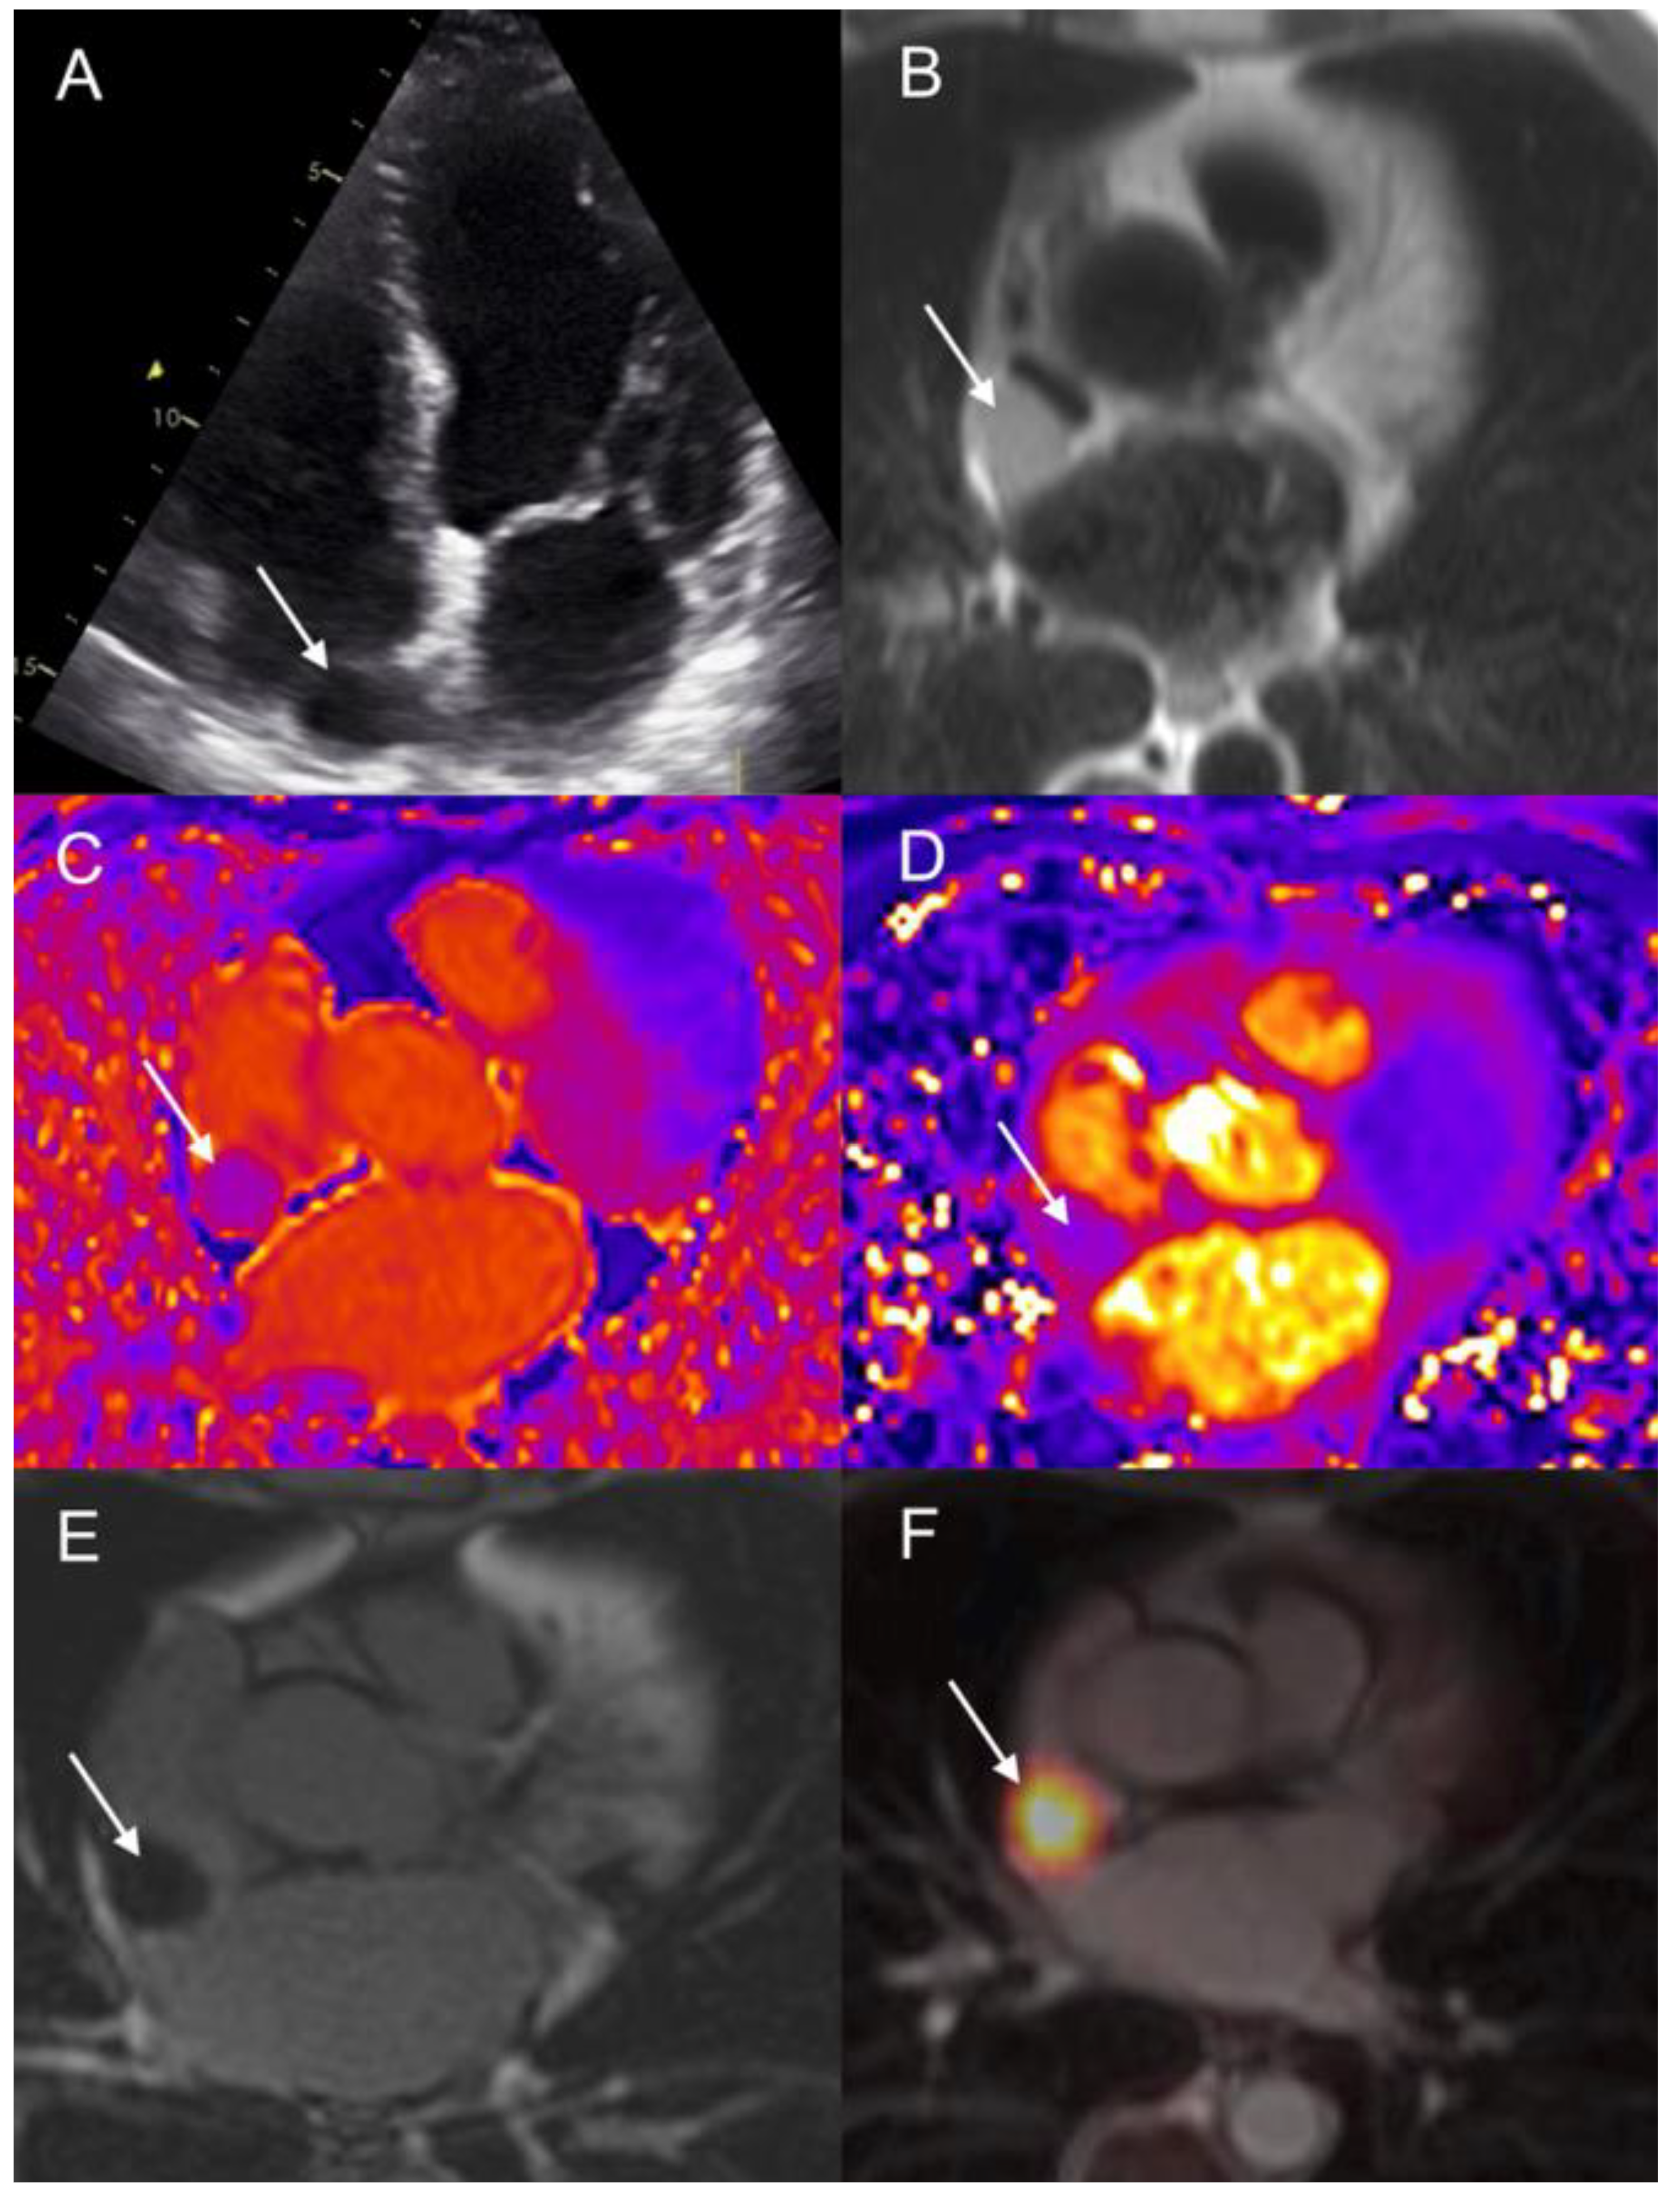

- 68Ga-DOTA-peptides and 18F-DOPA PET/CT are highly sensitive and specific for the initial diagnosis of CMs, which are usually detected incidentally during routine investigations;

- CMR and Cardiac-CT enable high-resolution, multiplanar imaging crucial for accurate anatomic localization, mass mobility assessment, and tissue characterization for noninvasive diagnosis confirmation;

- TTE remains clinically useful for cardiac function evaluation and tricuspid valve insufficiency detection (carcinoid heart disease), particularly in patients with functioning si-NETs and carcinoid syndrome;

- PET/MRI could represent a possible efficient “one-stop-shop” solution in patients with si-NETs.